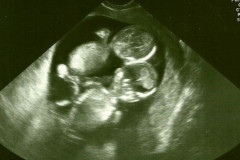

Доктор порекомендовал ей не говорить никому о беременности. Узнав причину, женщи... Гороскоп на неделю с 19 по 25 июня от астролога Веры Хубелашвили Новый образ первой леди США: Мелания Трамп на приеме в Белом доме Российская красавица выучила армянский, чтобы осуществить мечту Оказывается, зубная паста решает многие проблемы! 10 полезностей. Так картофель ты еще не готовила! Самый аппетитный гарнир, который я ела… Вот простой тест, чтобы узнать, сколько у вас будет детей Всю семью не пустили в Анталью из-за поведения наглого отца. Вот какие кадры про... Она закутала кусок хлеба вокруг своей ноги. Она не могла поверить, что случилось... Дочь назвала маму жирной. Ответ женщины вызвал горячую дискуссию в Сети Внимание! Если вы заметили эту этикетку на фрукте, ни в коем случае не покупайте... Этой фотографии 20 лет (Фото) Гарик Мартиросян о супруге: что она себе позволяет? Беременная проснулась в 3:30 ночи. Когда муж увидел, что происходит, то заорал н... Большая книга предсказаний: закройте глаза, задайте волнующий вас вопрос и откр... Победа превыше всего! Шокирующие моменты детских конкурсов красоты… (Видео) Первый муж Успенской рассказал, как они отказались от собственного сына Ваш стиль вождения может многое рассказать о вашем характере Брат этой девушки погиб в автокатастрофе. Через 10 лет в ее день рождения родите... 22-летняя повариха пошла к дантисту с абсцессом, но по итогу осталась без глаза Один из самых знаменитых нарядов принцессы Дианы назвали “платьем мести”. И вот ... ВЫБЕРИТЕ КАРТУ И УЗНАЙТЕ, НА КАКОМ ЭТАПЕ ЖИЗНИ ВЫ НАХОДИТЕСЬ! Крокодил укусил дрессировщика за голову на глазах у туристов (Видео) Когда он укусил помидор, то увидел, что внутри него… клубника! Вот чем оказался ... У новорожденных близнецов Бейонсе возникли проблемы со здоровьем? Гороскоп покупок на лето. Хватайте деньги и бегом в магазин! Дюймовочки нашего времени: знаменитости, чей рост меньше 160 см Щеки - минус 5 см (Фото) Какая она,жизнь известного , публичного человека «Ты что, тупая?!»: Роза Сябитова публично оскорбила Ларису Гузееву